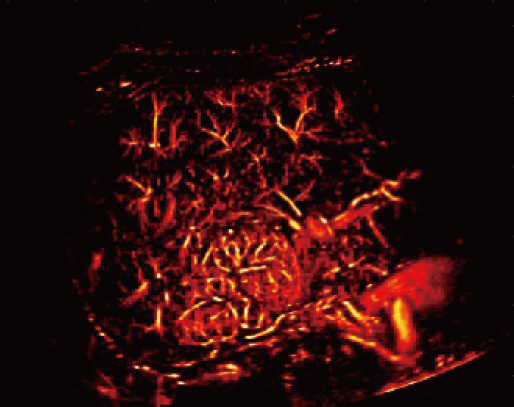

Dotato di un'ampia gamma di tecnologie di imaging innovative, Resona A20 supporta i medici nella ricerca clinica all'avanguardia. La Super Resolution CEUS (SR CEUS) rivela i dettagli della perfusione sanguigna a livello di micron, aiutando i medici nell'esplorazione delle prime alterazioni microcircolatorie nelle lesioni. Inoltre, la visco-elastografia STVi, una tecnica innovativa per la valutazione della viscosit├Ā dei tessuti, dimostra un grande potenziale per gli studi sulle malattie croniche del fegato e sui tumori.

Grazie alla piattaforma AIT, Resona A20 offre una soluzione integrata completa per l'imaging a super-risoluzione, una capacit├Ā finora difficile da raggiungere. La SR CEUS rivela i dettagli intricati del microcircolo delle lesioni a livello di micron, favorendo gli studi di perfusione microcircolatoria in oncologia.

Risoluzione a livello di micron

Capacit├Ā di rilevamento microvascolare

Iperplasia nodulare focale | Mappa densit├Ā

Iperplasia nodulare focale | Mappa direzione

Iperplasia nodulare focale | Mappa velocit├Ā